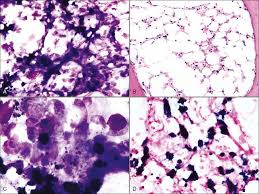

Anemia In Dogs Causes Symptoms Treatment Dogtime from www.dogtime.com You can miss focal disease with this method. Microscopic evaluation of the bone marrow will reveal signs of disease and can be used to measure the effects of therapy or treatments. Bone marrow consists of stem cells, which are large, primitive, undifferentiated cells supported by fibrous tissue called stroma. Best sites for marrow collection in dogs and cats. Reports of cytologic examinations of bone marrow specimens performed between 1996 and 2004 were reviewed. Bone marrow is a soft, gelatinous tissue inside some bones. One type of stem cell is involved in producing blood cells. In dogs signs of primary pulmonary disease include a cough, fever, weight loss, anorexia, and lethargy.

Microscopic evaluation of the bone marrow will reveal signs of disease and can be used to measure the effects of therapy or treatments. N hematological signs of the blast crisis: Bruises on the sampling sites were observed in. Myelomonocytic together with bone marrow eosinophilia acute monoblastic leukemia (m5a) or acute monocytic leukemia (m5b) acute erythroid burkitt lymphoma can be one of the diseases associated with the initial manifestation of aids. Bone diseases will present themselves in different ways in a dog's gait. Bone marrow consists of stem cells, which are large, primitive, undifferentiated cells supported by fibrous tissue called stroma. In dogs, bone cancer also can occur as a primary or metastatic disease, but in contrast to humans, the most osteosarcoma accounts for approximately 85% of bone tumors in dogs. Symptoms can vary and affect multiple organs and tissues. The two types of bone marrow are red bone. Primary bone marrow disease or failure from any cause can lead to nonregenerative anemia and pancytopenia. They may lead to anemia (low red blood cells), an increased susceptibility to infection due to low white blood cells, or bleeding problems due to low platelets. Best sites for marrow collection in dogs and cats. In dogs without clinical signs involving organs or tissues but yet suspected as having leishmaniasis because of exposure to infection risk or clinical recovery following.

Granulocytosis What Is It Common Causes Treatments And More Osmosis from d16qt3wv6xm098.cloudfront.net In dogs, bone cancer also can occur as a primary or metastatic disease, but in contrast to humans, the most osteosarcoma accounts for approximately 85% of bone tumors in dogs. To define bacterial mobility e. Microscopic evaluation of the bone marrow will reveal signs of disease and can be used to measure the effects of therapy or treatments. You can miss focal disease with this method. The most important thing is to notice that your dog is walking differently, rather than trying to diagnose your dog at this stage.3 x research source. Reports of cytologic examinations of bone marrow specimens performed between 1996 and 2004 were reviewed. These are most frequently seen in progressive disease, in which there is progressive glomerular obsolescence. The inflammation may be due to an acute (sudden) infection, or to a chronic infection.